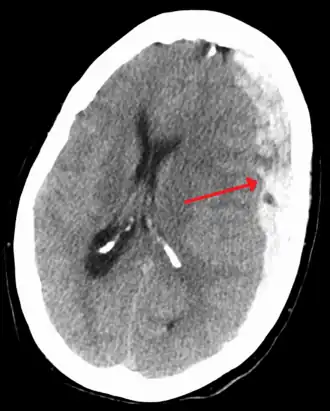

Image d'un hématome sous-dural, une des conséquences possibles du fait de secouer un bébé.

Le syndrome du bébé secoué (SBS)  ou Traumatisme crânien infligé par secouement (TCIS)[1]  est un ensemble de signes cliniques concernant un nourrisson : hématome sous-dural, hémorragie rétinienne, œdème cérébral, ce que l'on appelle parfois la « triade ».

Hématome sous-dural

Les hématomes sous-duraux sont répartis en plusieurs foyers. Uni- ou bilatéraux, ils se situent, dans la forme la plus caractéristique, dans la faux du cerveau et/ou la tente du cervelet. La prédominance de l'hématome associé à la présence de caillots au vertex est très évocatrice du diagnostic.

Ces hématomes ne sont pas toujours visibles initialement car ils peuvent être masqués au début par un œdème cérébral.